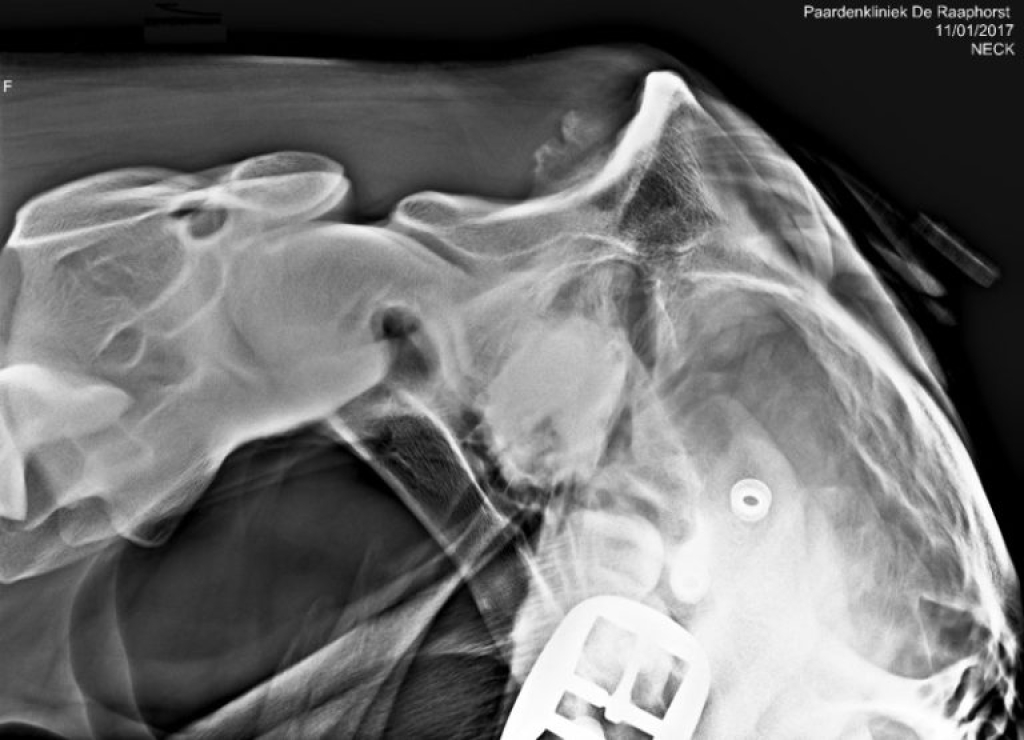

Echobeeld en röntgenfoto van het achterhoofd

Foto: Echobeeld en röntgenfoto van het achterhoofd

Het afvoelen van het gebied van de aanhechting van het ligamentum nuchae leidt niet altijd tot een duidelijke pijnreactie. Om de diagnose te kunnen stellen is het daarom nodig om het gebied in beeld te brengen met röntgenfoto’s en een echo. Omdat veranderingen die we waarnemen met röntgen en echo niet altijd in relatie staan tot klinische problemen kunnen de beelden nooit los gezien worden van de klachten bij het paard. Belangrijk hierbij is de mate van botbeschadiging, botactiviteit en of ook de aanhechting van de semispinalispees betrokken is. Zo zien we veel paarden met een onregelmatige botbelijning van het achterhoofd, zonder dat deze klachten hoeven te hebben.

Links: Röntgenfoto van benige nieuwvorming op het achterhoofd

Röntgenfoto van benige nieuwvorming op het achterhoofd